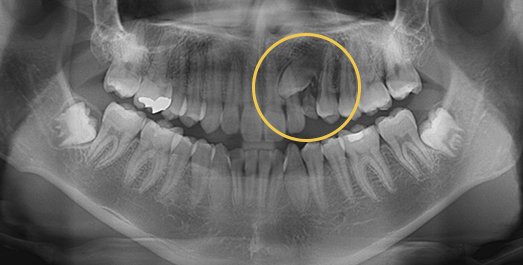

Impacted Tooth Solution

An impacted tooth remaining within the alveolar bone can cause damage to adjacent teeth. Orthodontic traction is used to guide the impacted tooth into its correct position,

allowing it to erupt and seat normally within the dental arch.

• BEFORE: 2011.08.12

• AFTER: 2013.07.08